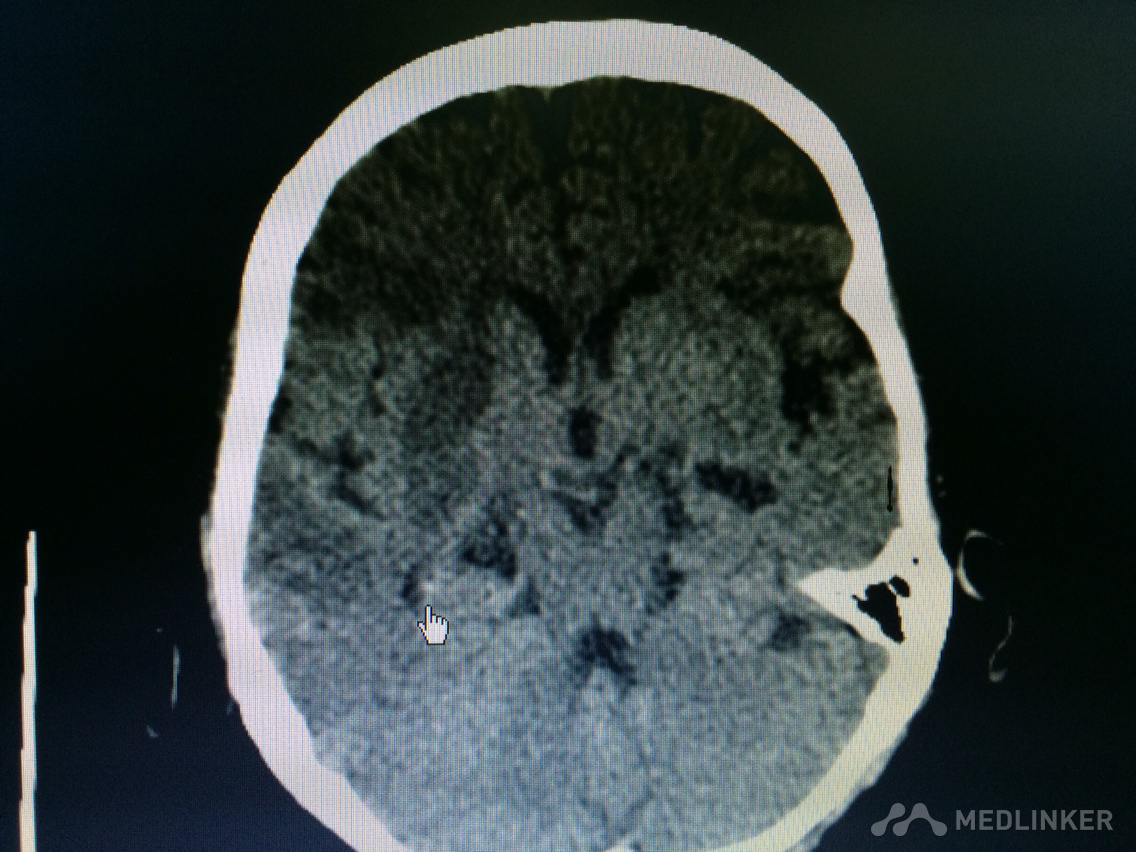

下面的CT梗塞灶,请问对应血管?